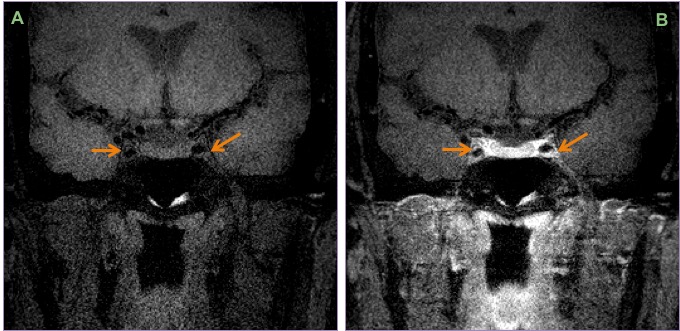

High resolution vessel wall imaging (A & B) shows eccentric enhancement involving the inferior wall of the cavernous left internal carotid artery and minimal concentric enhancement on the right.